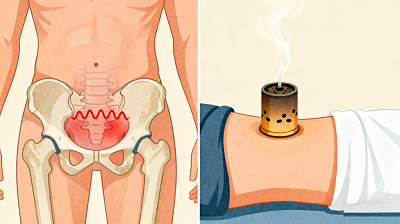

盆腔炎,是女性生殖道炎症及其周围组织的炎症,主要有子宫内膜炎、输卵管炎、输卵管卵巢脓肿、盆腔腹膜炎。炎症可感染一个部位,也会互相感染后几个部位都感染。盆腔炎的症状主要表现为白带增多、下腹坠胀疼痛、腰骰疼痛、或肛门坠胀、痛经、月经不调、不孕症、或伴有尿频。

盆腔炎最大的危害是造成不孕症。妇女盆腔内子宫、输卵管及卵巢或其周围的组织,包括盆腔内腹膜,任何一处发生炎症时,都可以造成妇女不孕。当急性炎症未能彻底治疗时转变成慢性,或者盆腔炎治疗不及时,迁延成慢性时,常常造成妇女不孕。盆腔炎引起的不孕症西医手段很难治疗,有些使用手术治疗的患者即便用手术治疗成功,也会因为炎症未能清除而无法根除症状。